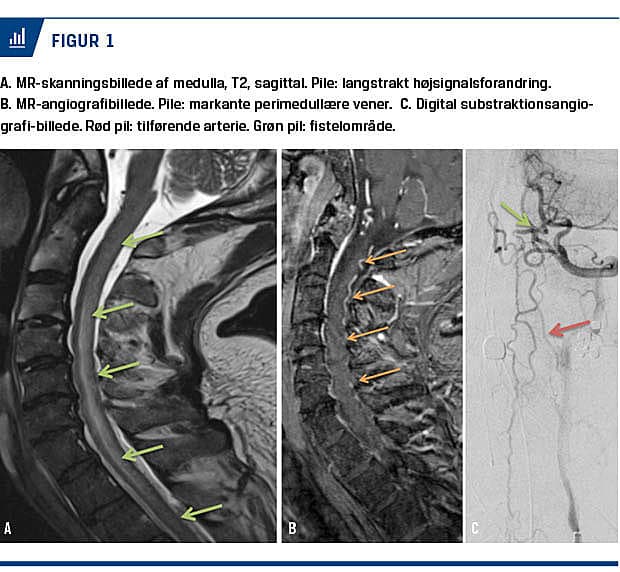

På MR-skanninger vil der ofte kunne ses langstrakt (over tre segmenter) transversel myelopati med inddragelse af størstedelen af medullas tværsnit, typisk i kombination med kontrastopladning og dilaterede perimedullære vener [1, 4]. Langstrakt transversel myelopati har en lang række diffentialdiagnostiske årsager, hyppigst inflammatoriske (primære eller sekundære i forbindelse med andre systemsygdomme), sjældnere infektiøse, maligne (herunder paraneoplastiske) eller øvrige vaskulære. Inflammatorisk langstrakt transversel myelopati uden kendt årsag benævnes idiopatisk transversel myelitis (TM).

MR-angiografi viste et forøget antal snoede vener cervikalt (Figur 1). Ved efterfølgende digital substraktionsangiografi (DSA) fandtes fistel fra venstre a. vertebralis med drænering til cervikale medullære vener (Cognard type V). Patienten blev endovaskulært behandlet med partiel embolisering og efterfølgende opereret med komplet lukning af fistlen bekræftet ved DSA.